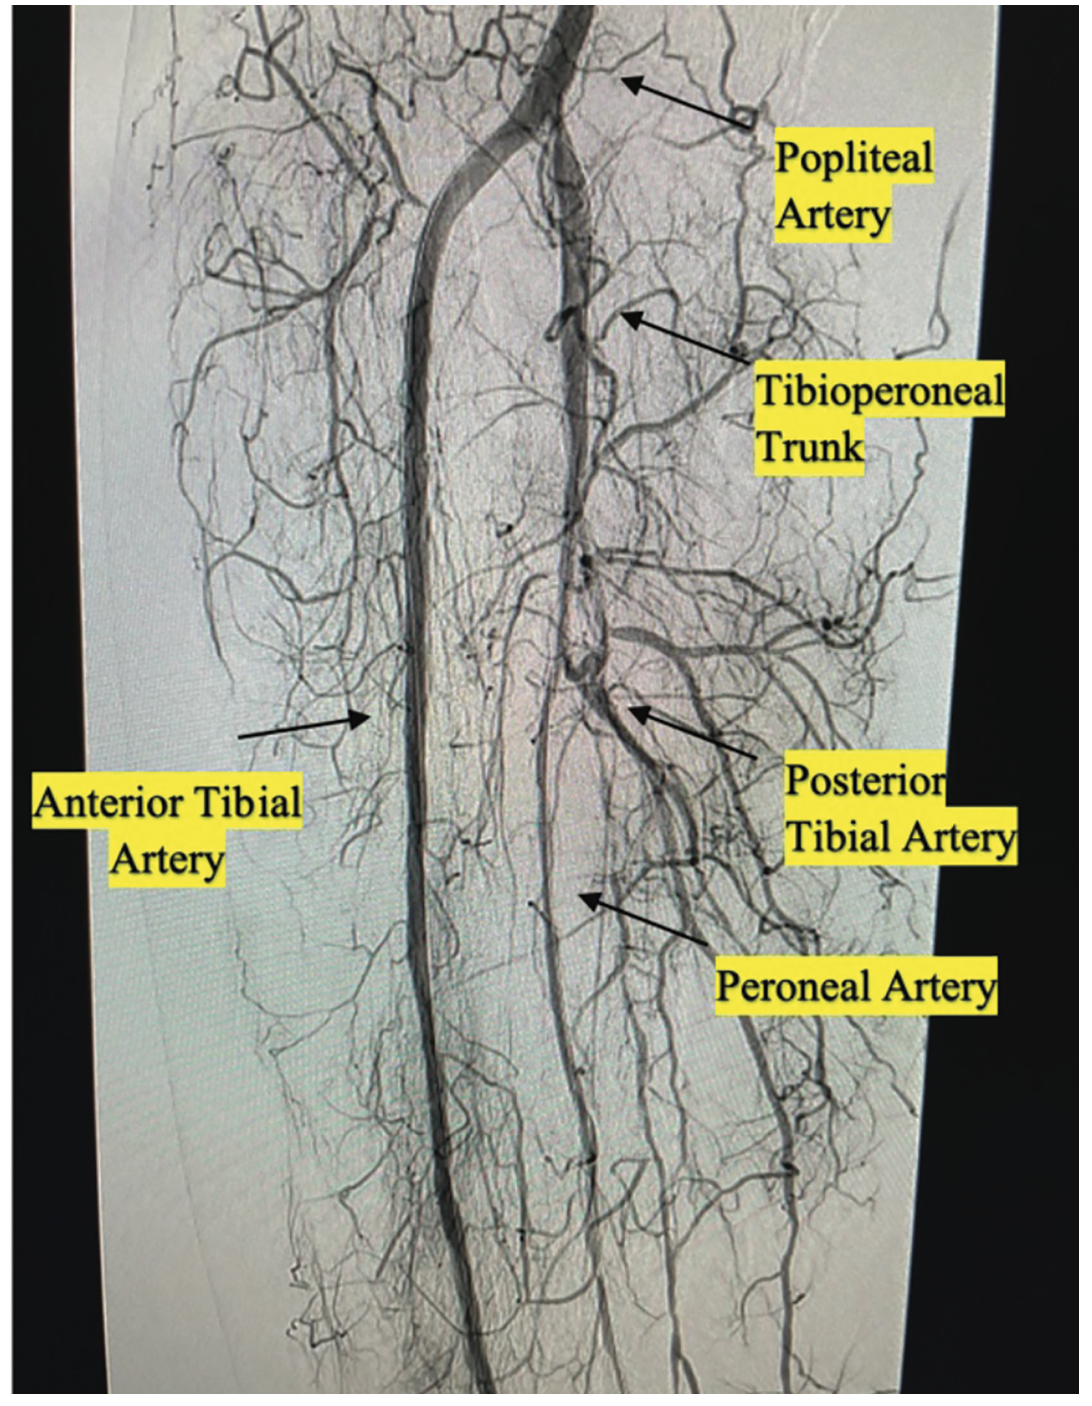

Transpedal right anterior tibial artery access was obtained using ultrasound guidance with a “dry stick”, and the initial angiogram through the sheath showed a chronic total occlusion (CTO) of the anterior tibial artery, with faint collateral flow to also-occluded peroneal and posterior tibial arteries (Figure 1). A subsequent selective angiogram was performed through a Rubicon support catheter (Boston Scientific), advanced from the transpedal sheath to the right external iliac artery. An angiogram with runoff to the foot showed the right SFA had a mid 100% CTO with in-stent restenosis. In addition, the anterior tibial artery was 100% chronically occluded, and the peroneal and posterior tibial arteries were 100% chronically occluded (Figure 2).

After reviewing the angiographic findings, the decision was made to intervene on the anterior tibial artery and SFA. Given the patient’s previous groin access complications along with his significant iliac tortuosity, we proceeded using only the single transpedal access obtained during the initial peripheral angiogram. An .009-inch Rotawire (Boston Scientific) was advanced into the right external iliac artery from the pedal sheath. We performed rotational atherectomy of the chronically occluded SFA and popliteal artery, followed by percutaneous transluminal angioplasty of the right anterior tibial artery and SFA CTO. At this point, we observed good flow in the right SFA and anterior tibial arteries, with a reduction of the stenosis from 100% to 0%. However, the tibioperoneal trunk was still occluded at the ostium (Figure 3). We attempted to advance several wires from the anterior tibial artery across the tibioperoneal trunk. We initially attempted to cross using our traditional peripheral wires, which include the Choice PT extra support (Boston Scientific) and Hi-Torque Command (Abbott Vascular) guidewires. Each attempt was unsuccessful, as the acute angle of the tibioperoneal trunk would cause the wires to prolapse into the popliteal artery. A 120-degree angled tip SuperCross support catheter (Teleflex) (Figures 4-5) was incorporated to help guide us across the acute angle of the occluded tibioperoneal trunk. However, the aforementioned peripheral wires would still prolapse into the popliteal artery and straighten the angled tip of the SuperCross catheter. We switched to a coronary Hi-Torque Whisper guidewire and using the 120-degree angled tip SuperCross support catheter to guide us across the acute angle of the tibioperoneal occlusion, the wire successfully advanced all the way down the peroneal artery (Figures 4-6). We advanced a 2.5 mm x 30 mm coronary Euphora balloon (Medtronic) over the wire and performed successive sequential balloon angioplasty of the proximal tibioperoneal trunk and the peroneal artery all the way to the ankle. An angiogram showed excellent flow post intervention, with 0% residual stenosis (Figure 6).